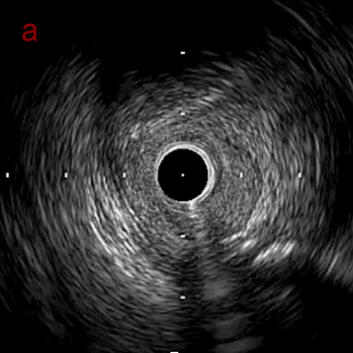

IVUS imaging

IVUSでは8時方向からPD枝がはいいてくる。

PreのIVUSではaの部位のみlipid plaqueを認め削ることでdistal embolismのリスクがあり、そのほかは270度の偏心性石灰化であるがwire biasは良好。

OAS low speedによる引きを赤線の区間行う方針とした。